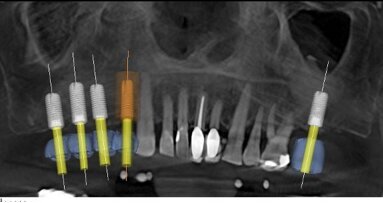

En 2005, j'écoutais un orateur discuter d’une nouvelle façon de positionner les implants dentaires qui révolutionnerait le ...

Afin de mieux comprendre toutes les possibilités offertes par l’implant Z1, un groupe d’enseignants, spécialistes des implants Z1 et TBR Dental, ...